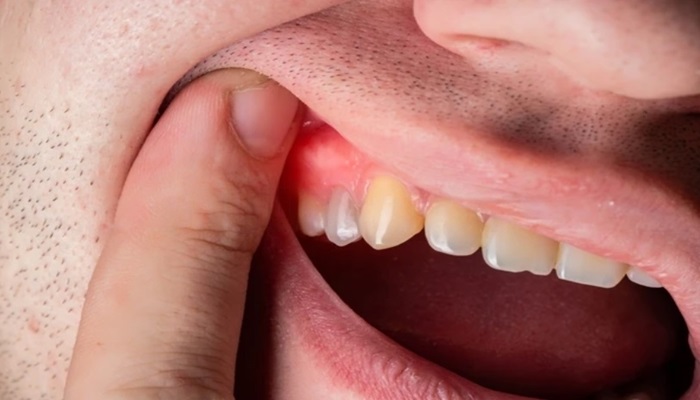

عفونت فعال دندان ممکن است باعث:

• انتشار عفونت

• درد شدید

• تب

• استرس فیزیولوژیک برای مادر

شود که این موارد می‌توانند ریسک بیشتری نسبت به خود درمان داشته باشند.

چرا درمان عفونت دندان در بارداری مهم است؟

عفونت‌های دهانی کنترل‌نشده ممکن است با:

• افزایش التهاب سیستمیک

• استرس فیزیولوژیک

• مشکلات عمومی سلامت مادر

مرتبط باشند.

بنابراین درمان به‌موقع معمولاً ایمن‌تر از نادیده گرفتن مشکل است.